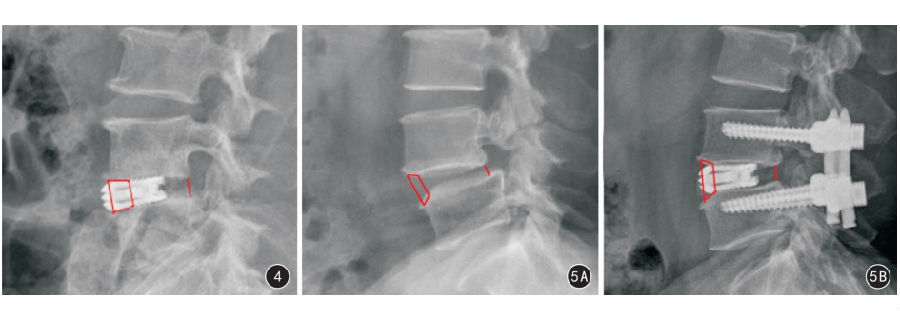

图1 腰椎失稳症患者侧位X线影像测量腰推间隙参数 a:椎间隙前缘高度,为相邻两椎体前缘点间的直线距离; b:椎间隙盘状小凹前端高度,为椎间隙盘状小凹两前缘点间的直线距离;c:椎间隙后缘高度,为相邻椎体两后缘点间直线距离 图2 测量方法 2A 将Philips Dicom Viewer软件的定位线工具定位于椎体横断面CT影像 2B 与2A相对应的椎体冠状面CT影像 2C 在椎体冠状面影像上做中心线,取椎体两侧最高点(双头箭)做连线,测量椎体中心线与椎体接触点至椎体两侧最高点连线的垂直距离 图3 腰椎失稳症病变椎间隙X线测量分型 3A AD型 3B AE型 3C BD型 3D BE型 3E CD型

图4 患者女,56岁,腰椎失稳症患者,行后路镜下端膨胀融合器置入融合术。术后3个月X线片示端膨胀融合器在AD型椎间隙中的置入位置,稳定性好 图5 患者男,52岁,腰椎失稳症合并I度腰椎滑脱患者,行后路镜下端膨胀融合器置入融合术联合经皮椎弓根钉内固定术 5A 术前侧位X线显示为AD型 5B 术后3个月侧位X线片显示转为AE型